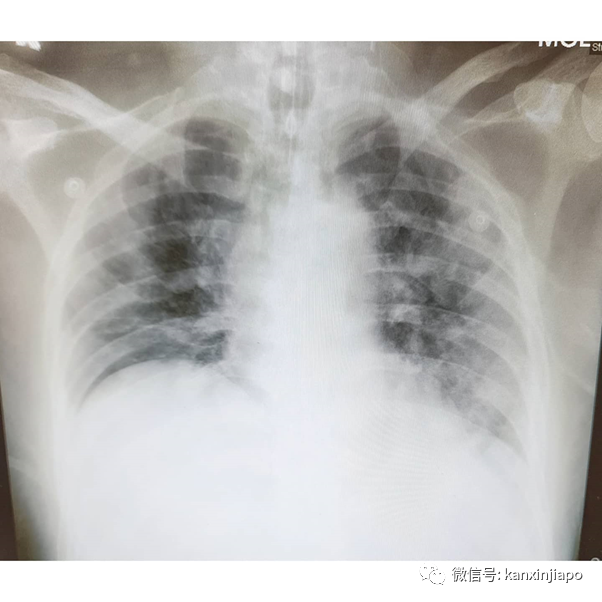

Covid19对肺部造成的伤害很大,并非普通的伤风感冒。